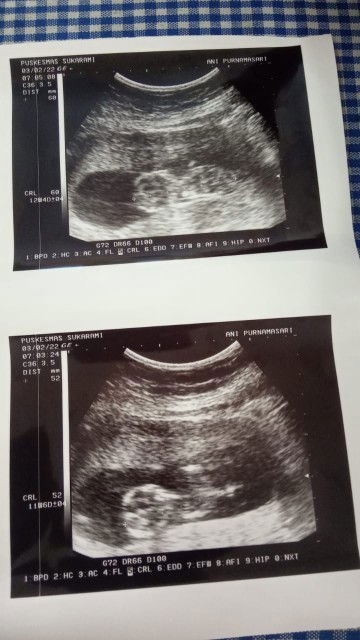

Bentuk usia bayi 4bln

Saya ingin mengetahui bentuk calon baby saya usia kandungan 4 bln

bentuk nya ya begitu Bun,dokter ngejelasin gak pas USG tentang perkembangan bayi bunda